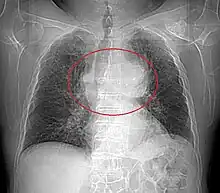

Radiographie thoracique

La radiographie thoracique permet de visualiser entre 45 % et 80 % des tumeurs thymiques[29]. De face, elles présentent un aspect bien délimité, parfois lobulé, débordant d'un côté du médiastin. Le profil permet d'affirmer le caractère rétrosternal de la tumeur, et donc sa localisation dans le médiastin antérieur. Les signes d'envahissement sont rares et peu visibles, et comprennent principalement l'ascension d'une coupole diaphragmatique, faisant suspecter un envahissement du nerf phrénique[28].